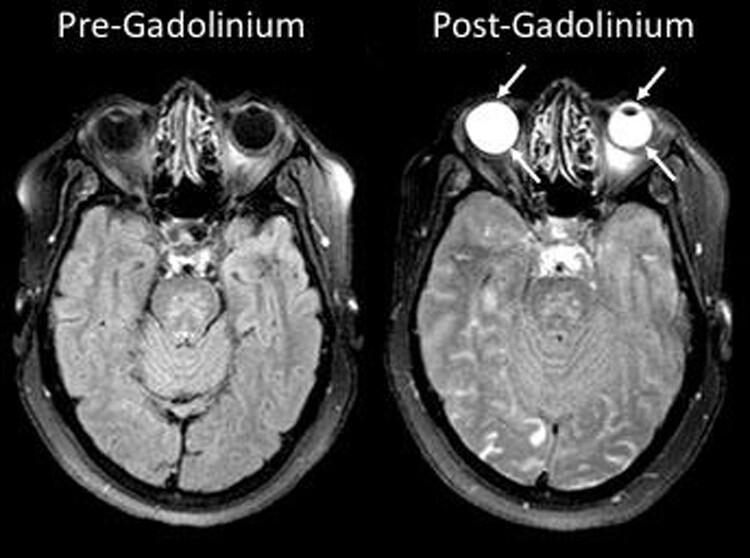

Pupillary Responses Stanford Medicine 25 Stanford Medicine